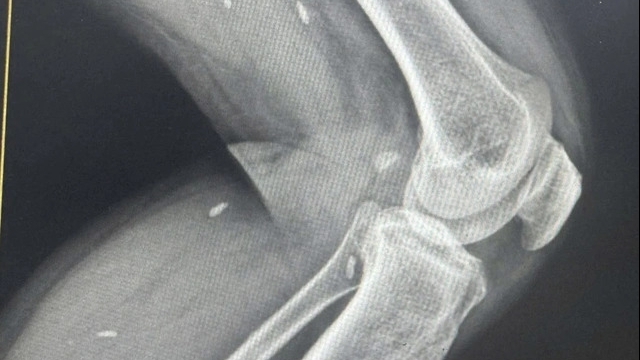

Qua kiểm tra, Đoàn ghi nhận: Khoảng 12 giờ ngày 1/8, sau khi ủ tê, bà B. H. C tiêm filler vào vùng trán phải bệnh nhân. Sau tiêm khoảng 1 phút, bệnh nhân bị mờ mắt phải. Bà C liền tiêm thuốc giải cho bệnh nhân, đồng thời đưa người bệnh đến cấp cứu tại bệnh viện với chẩn đoán: Mắt phải viêm màng bồ đào toàn bộ, tắc động mạch trung tâm võng mạc; Theo dõi thiếu máu da vùng trán phải, mắt phải, mũi sau tiêm filler.